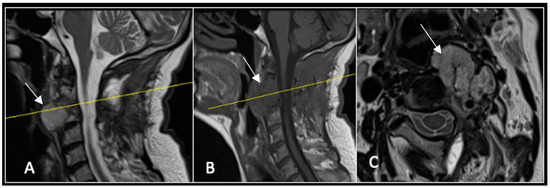

2.3. Case 3: Cervical Chordoma

This 68-year-old male was referred to our institution with a 4 cm cervical mass localised to C2/3 following investigations for left-ear congestion and altered hearing (Figure 7). A CT-guided biopsy confirmed a conventional chordoma. The patient underwent separation surgery with adjuvant proton beam therapy. There was no evidence of disease progression on 3-monthly surveillance imaging (Figure 8). Approximately 12 months following separation surgery, the patient presented with acute onset neck pain. A C2 odontoid peg fracture was diagnosed requiring a posterior occipitocervical stabilisation procedure (Figure 9). Pre-stabilisation MRI imaging confirmed no tumour progression (Figure 10).

Figure 7.

The MRI demonstrates a left-sided lobular mass (arrow) with invasion of the C2/3 vertebral body and epidural extension, but no cord compression. The yellow line on the axial image indicates the axial slice level. (A) T2W sagittal; (B) T1W sagittal; (C) T2W axial.

Figure 8.

MRI demonstrating a left-sided posterior approach to the cervical spine with significant reduction in residual gross tumour volume (arrow) and circumferential decompression of the spinal cord. The yellow line on the sagittal images denotes the level corresponding to the axial section. (A) T2-weighted sagittal; (B) T1-weighted sagittal; (C) T2-weighted axial.

Figure 10.

RI demonstrating no tumour (arrow) progression with wide circumferential margins around the spinal cord. The yellow line on the sagittal images represents the level of the axial plane. (A) T2W sagittal; (B) T1W sagittal; (C) T2W axial.